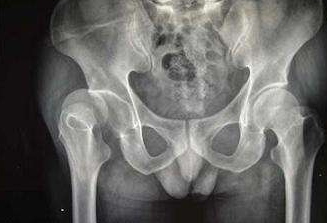

髋关节的僵硬局部肌肉的萎缩疼痛晚期股骨头坏死怎么

郑州骨科病医院介绍对于股骨头坏死晚期的病人,主要还是表现为髋关节的僵硬、局部肌肉的萎…[详情]